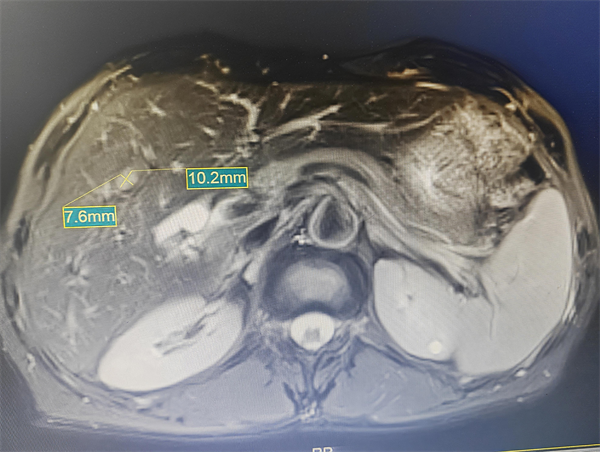

患者舒某某(化名),今年70岁,2021年曾因肝细胞癌在我院行“肝VII、VIII段切除”,术后一直定期在我院随访,今年5月份复查时,肝脏磁共振检查发现一直径约10mm的可疑结节,增强磁共振考虑肝癌复发。鉴于患者合并乙肝肝硬化、尘肺,且有既往开放手术史,综合考虑其肿瘤特点,经多学科专家团队术前充分评估与深入讨论,最终制定了超声引导下肝肿瘤微波消融术的个性化治疗方案,并决定应用超声造影技术,在术前、术后对肿瘤进行全面评估,确保消融效果。